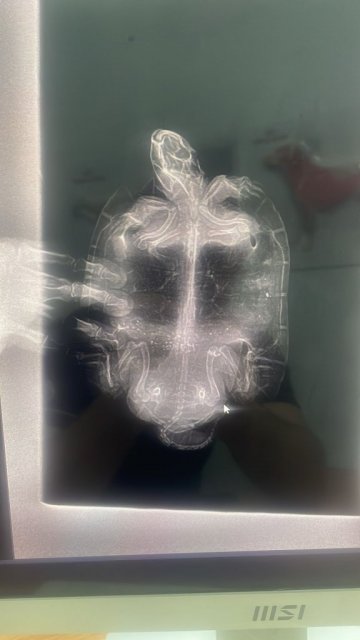

Добрый день! Наш самец 15 лет (20 см карапакс), 900 гр, наелся герметика с мелкими камешками, которым покрыт островок. В пн поел как обычно, во вторник тоже, а в среду после кормешки срыгнул всю еду. С едой вышли два куска герметика размером с пятак. В четверг срыгнул остатки еды и еще два длинных куска герметика. От еды оказывался в чт. В пт съел кусочек рептомина. В пт после обеда отвезли в ветклинику. Сделали рентген. Врач сказала, что нет закупорки. Сегодня вс третий день носим в клинику на уколы (комплекс витаминов и антибиотик). Сделали клизму. Все вышло. Врач уверяет, что нет закупорки. Вялый. Поел 6 кубиков мотыля. Но сам не просит еду как обычно. Пока не видели помёт. В среду, после того как стошнило, он испражнился большой зеленой плотной какулей размером с палец большой. Это рептомин с прошлой пятницы видимо вышел. Больше помет не видел. Но он и не ел толком. Немного мотыля с субботы. Жду помет. Попросил сделать контрастный снимок. Врач отговорил, сказала барий опасен для черепахи, может умереть. Что делать? Помогите пожалуйста. Очень люблю этого зверька. Он офисный, корпоративный. 15 лет ему уже.